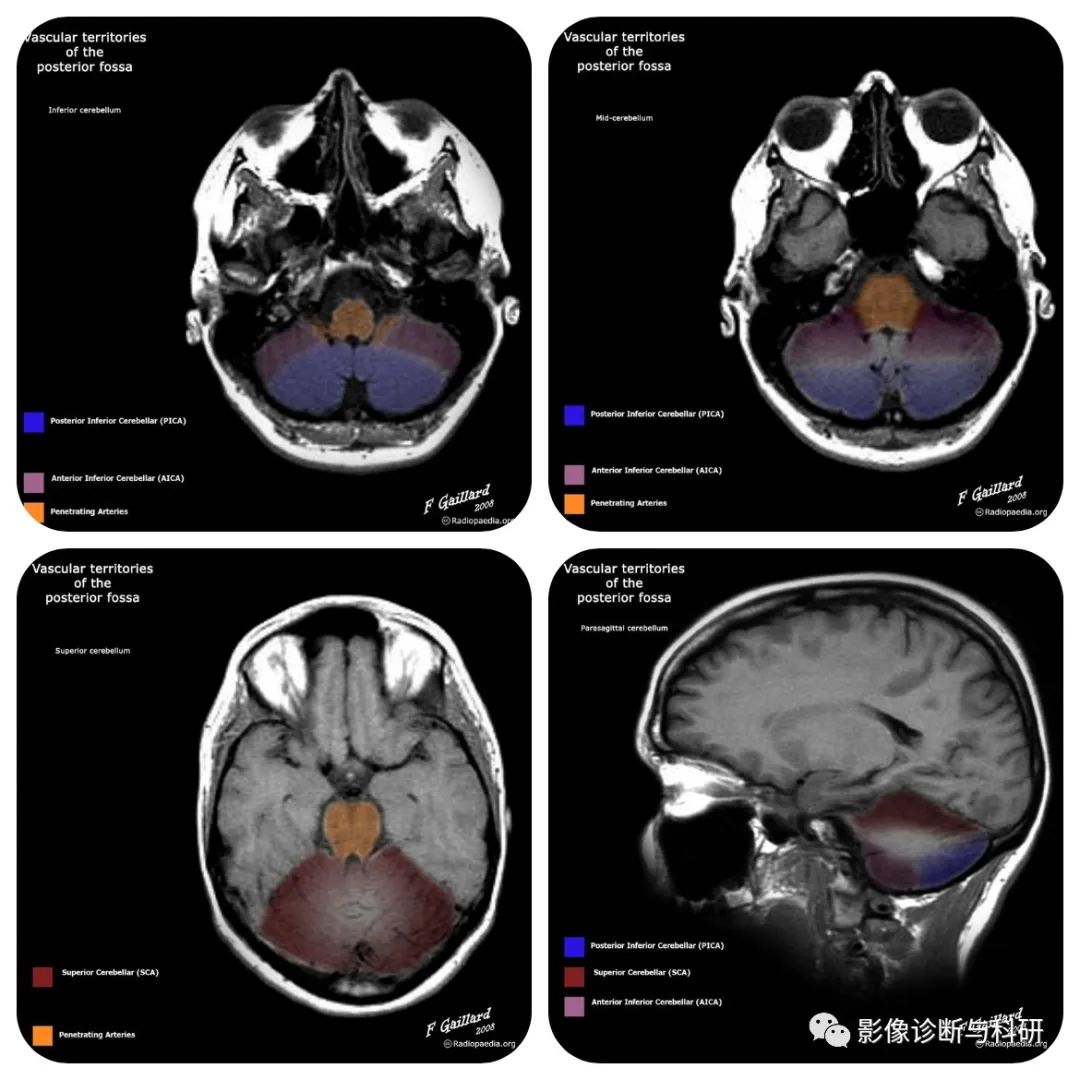

一、小脑动脉解剖

1.小脑上动脉(SCA):小脑上动脉为基底动脉的分支,主要营养小脑上面,即供应小脑半球上面、小脑蚓部上部、前髓帆等。

2.小脑下前动脉(AICA):小脑下前动脉主要营养小脑下面的前部,99%起源于基底动脉,但具体位置可有不同:75%起源于基底动脉下三分之一,16%起源于基底动脉中三分之一,9%与椎基底动脉连接。